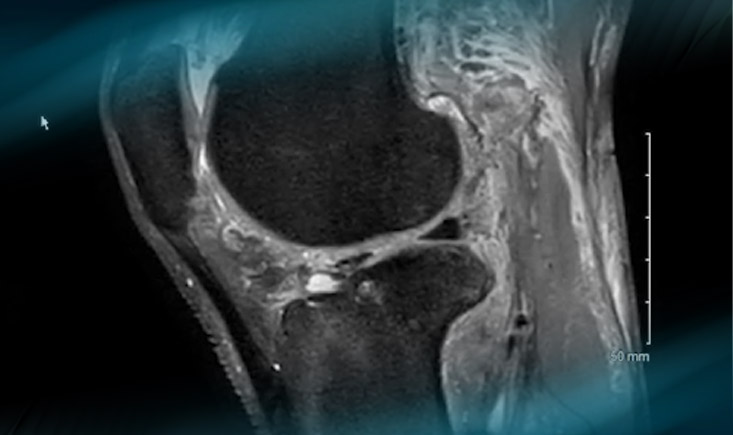

The ACL Rupture

Imagery MRI